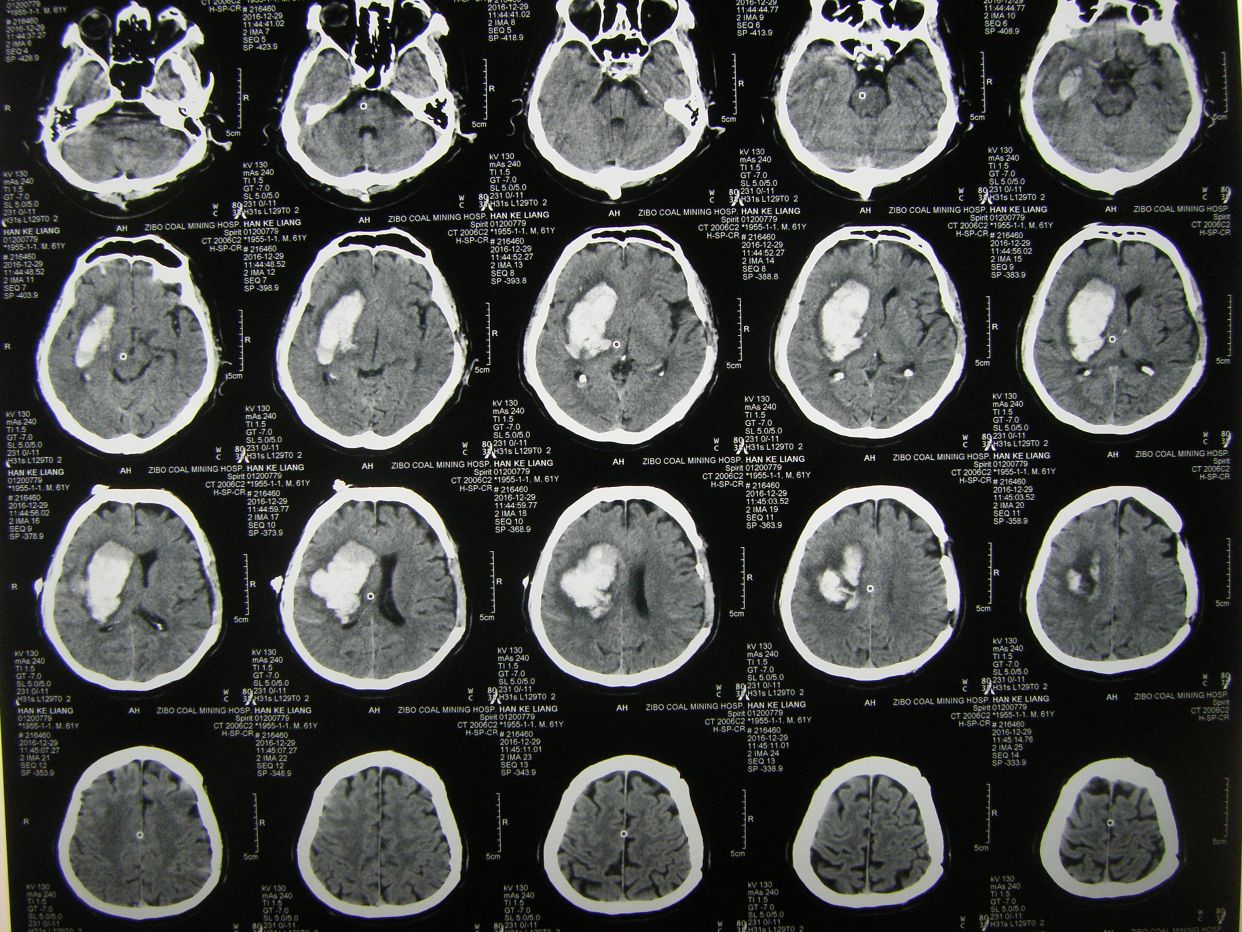

因呼吸急促,氧饱和度低,行胸部CT检查示,双肺野弥漫性斑片状阴影,保留气管插管,拍背吸痰,加强供氧,应用抗炎平喘化痰等药物治疗。

术后半月胸部CT复查示,肺部阴影消退。患者体温血象正常,神志清,遵嘱动作,右侧肢体肌力3级,出院康复。